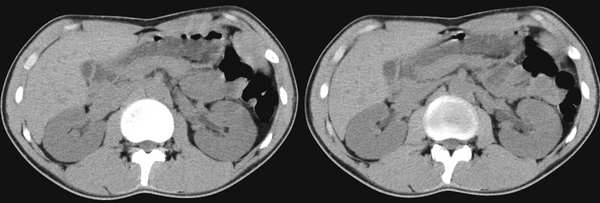

男,23岁,腰痛一个月,彩超示双侧肾盂分离

肾ct平扫未见异常

肾盂或肾窦分离是b超上的术语,而ct上看不出来,故ct报告未见明显异常

还是做个ivp吧除外双肾盂,本例ct未见明显异常。

认为是正常的肾脏,肾盂没有见分离征象。